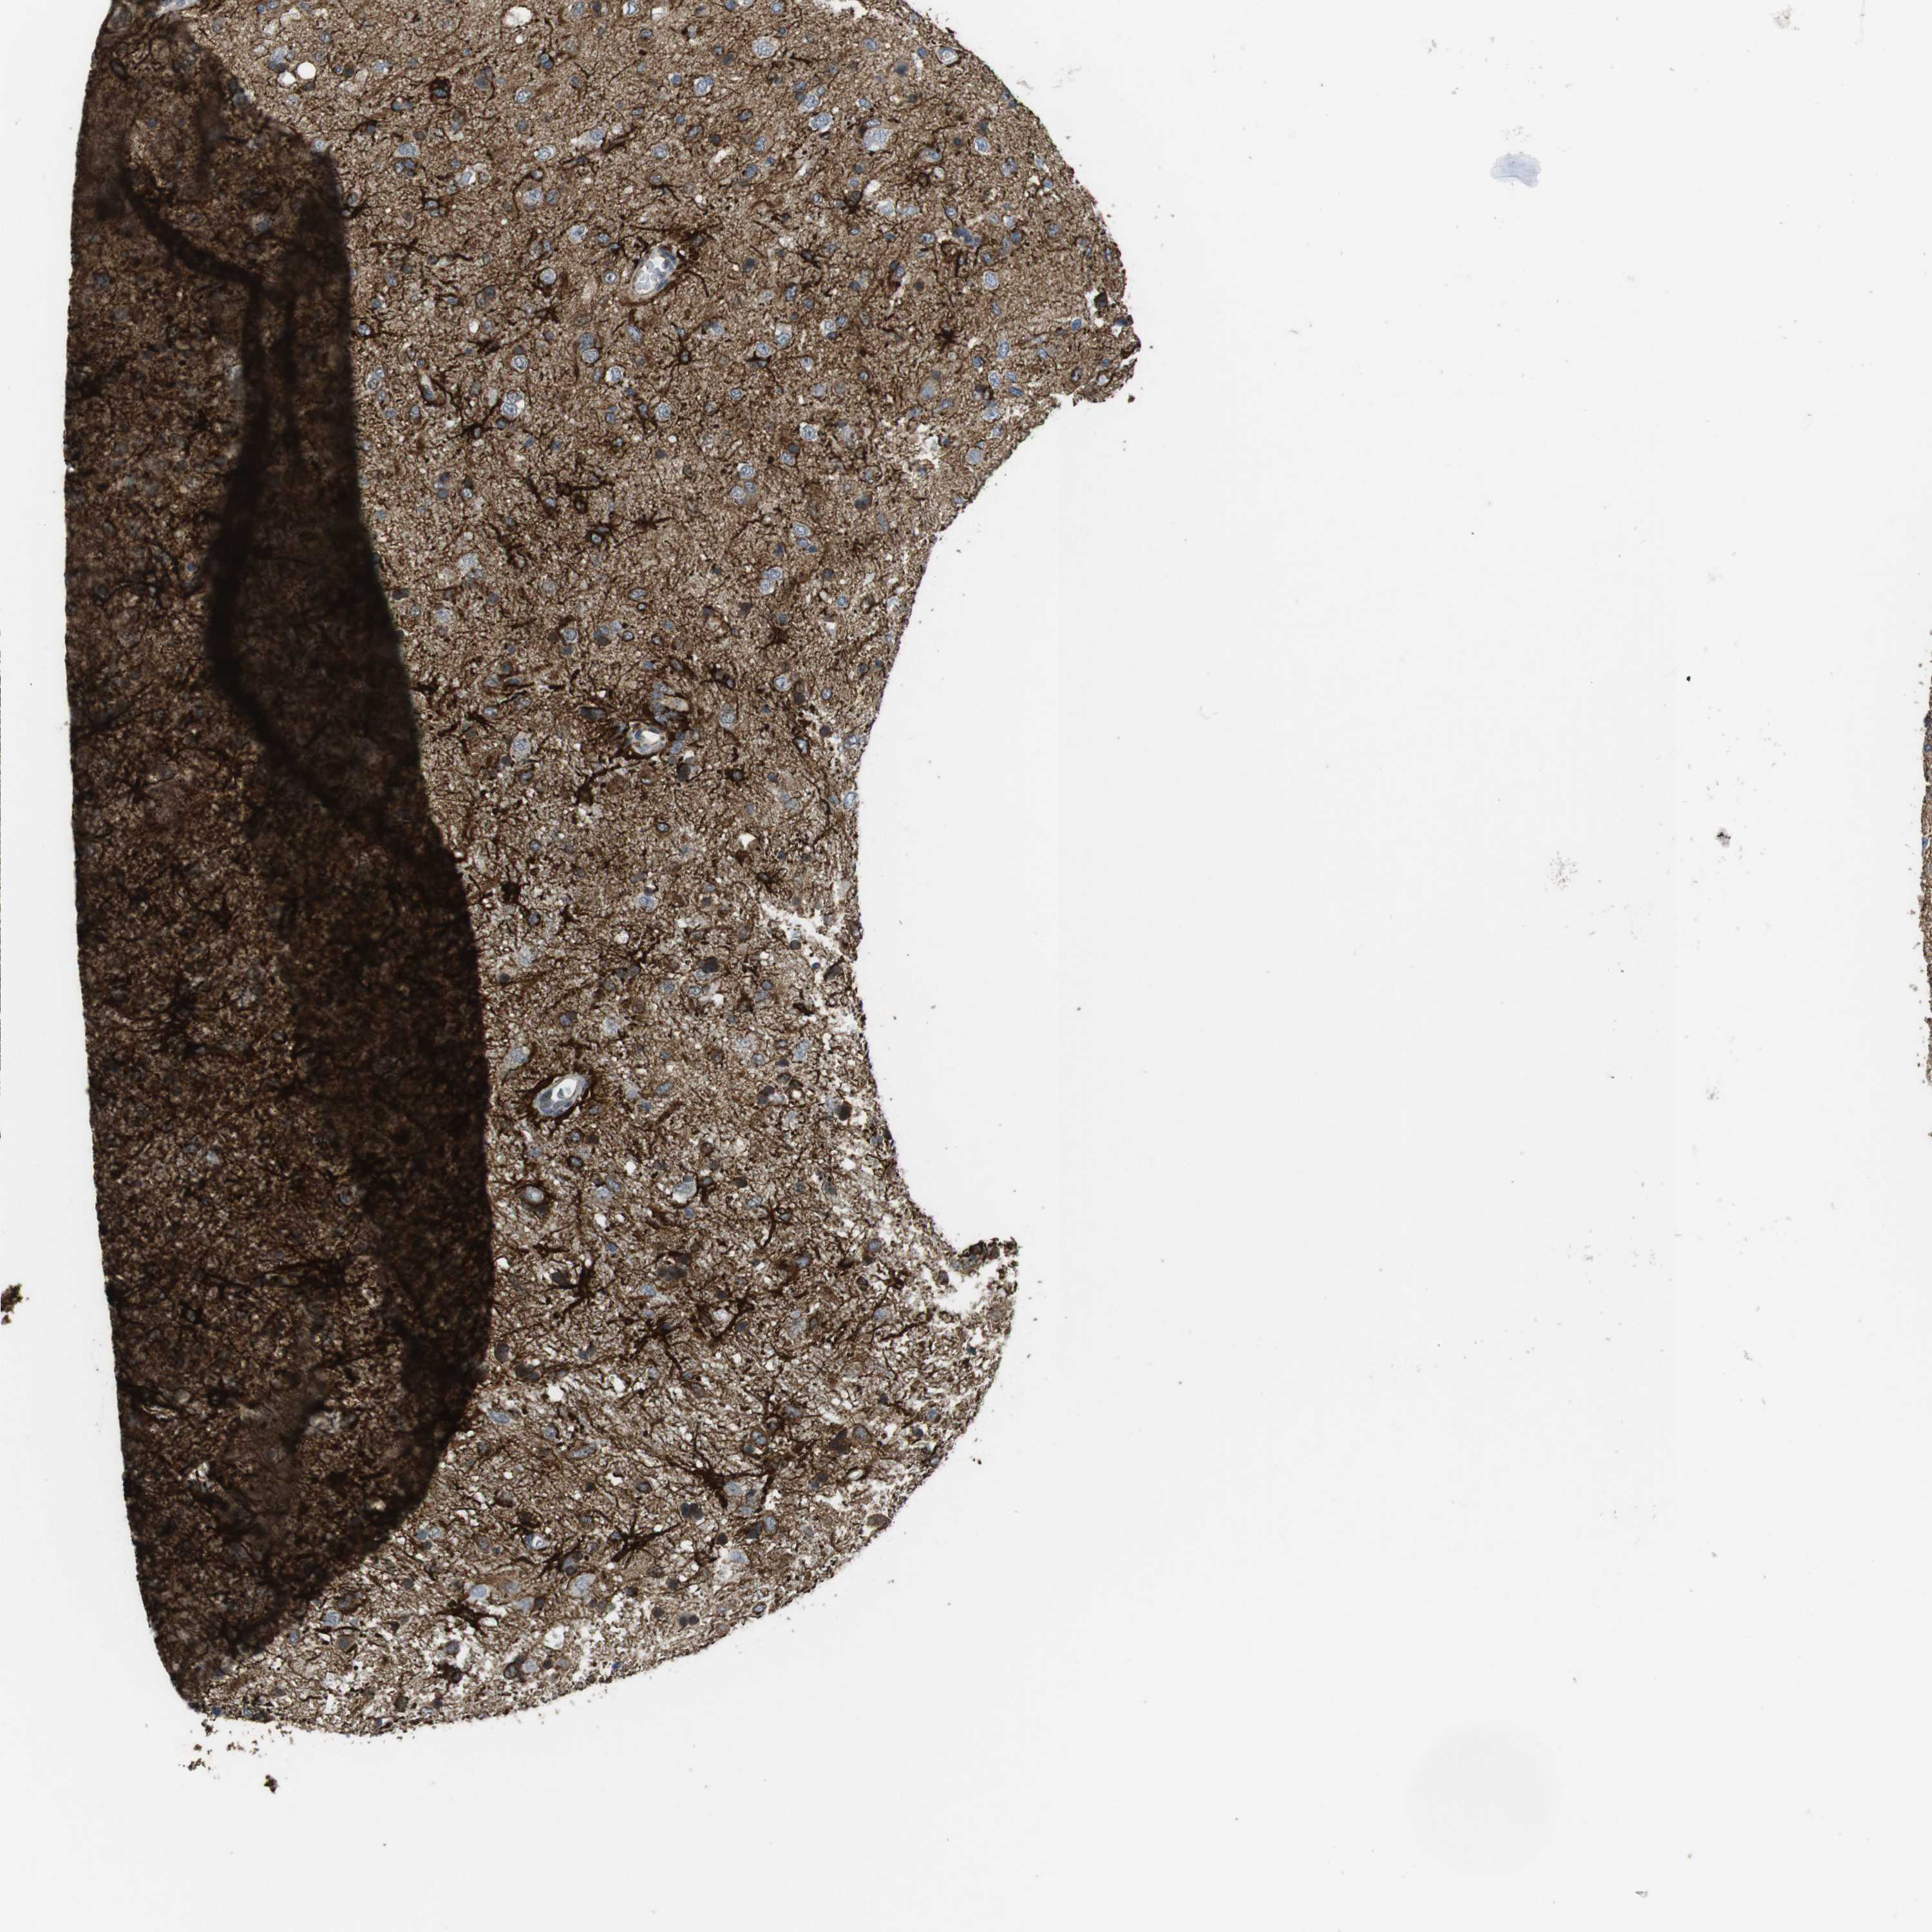

GLIOMA - Protein expressioni

A mouse-over function shows sample information and annotation data. Click on an image to view it in a full screen mode. Samples can be filtered based on level of antibody staining by selecting one or several of the following categories: high, medium, low and not detected. The assay and annotation is described here.

Note that samples used for immunohistochemistry by the Human Protein Atlas do not correspond to samples in the TCGA dataset.

Antibody stainingi

Antibody staining in the annotated cell types in the current human tissue is reported as not detected, low, medium, or high, based on conventional immunohistochemistry profiling in selected tissues. This score is based on the combination of the staining intensity and fraction of stained cells.

Each image is clickable and will lead to virtual microscopy that enables deeper exploration of all samples and also displays staining intensity scores, fraction scores and subcellular localization as well as patient and tissue information for each sample.

Antibody HPA026846

Antibody CAB016135

Staining

High

Medium

Low

Not detected

Intensity

Strong

Moderate

Weak

Negative

Quantity

>75%

75%-25%

<25%

None

Location

Nuclear

Cytoplasmic/membranous

Cytoplasmic/membranous,nuclear

Glioma, malignant, High grade

Glioma, malignant, Low grade